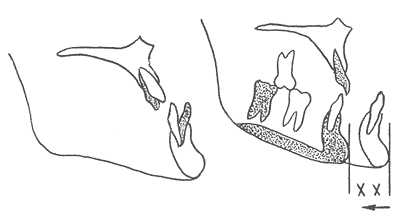

3.1.1 改正患者原有的牙代偿,将上、下颌牙正确地排列在他们相应的基骨上。如下颌前突的患者,其上、下前牙代偿,即上前牙前倾,下前牙舌倾。为手术后退下颌而准备时,应内收上前牙,直立(唇倾)下前牙而去除其代偿。由于去了牙代偿,反超

加大,手术时下颌骨才能退到正常位置,保证术后咬合协调、面部美观及

的稳定(图1,2)。

图1 牙未去代偿下颌后退少

图2 牙去代偿、下颌后退充分